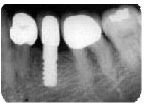

これは私の手術したインプラント。

貝殻の代わりにチタンでできた人工の根を埋め込みました。